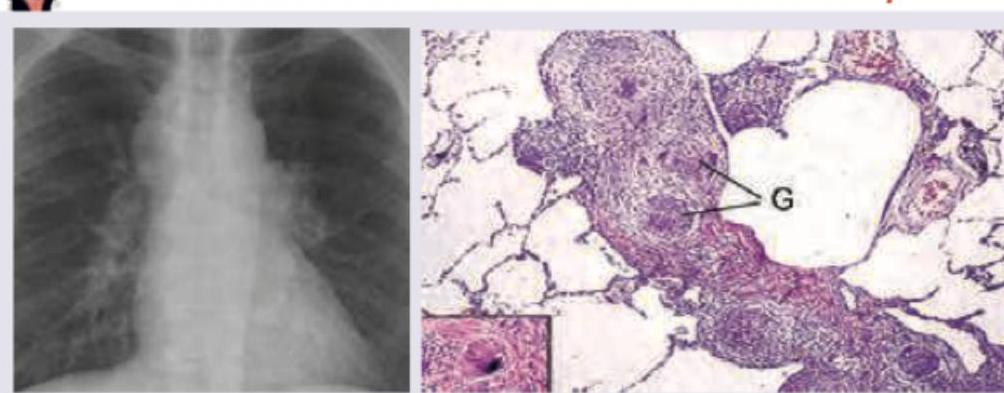

Explanation: ***Bilateral hilar lymphadenopathy with caseating granulomas*** - Sarcoidosis, depicted in the images (bilateral hilar lymphadenopathy on chest X-ray and **non-caseating granulomas** on histology), is characterized by **non-caseating** (not caseating) granulomas. - **Caseating granulomas** are typical of tuberculosis and certain fungal infections, not sarcoidosis. *Kveim-Siltzbach procedure is an intradermal test* - The Kveim-Siltzbach test is an **intradermal injection** of sarcoidosis tissue extract, which would reliably induce a granulomatous reaction in patients with active sarcoidosis. - While historically used, it is now rarely performed due to unavailability of standardized antigen and the risk of disease transmission. *Increased CD4/CD8 Ratio >3.5 in Bronchoalveolar Lavage* - An elevated **CD4/CD8 ratio**, typically greater than 3.5, in **bronchoalveolar lavage (BAL)** fluid is a characteristic finding in active pulmonary sarcoidosis. - This indicates an accumulation of helper T cells in the lungs, contributing to granuloma formation. *Lofgren syndrome leads to uveitis* - **Löfgren syndrome** is an acute form of sarcoidosis characterized by the triad of **hilar lymphadenopathy**, **erythema nodosum**, and **arthralgia**. - While it is a specific presentation of sarcoidosis, **uveitis** is also a known manifestation of sarcoidosis but is not a defining characteristic of Löfgren syndrome itself; however, sarcoidosis can cause uveitis.